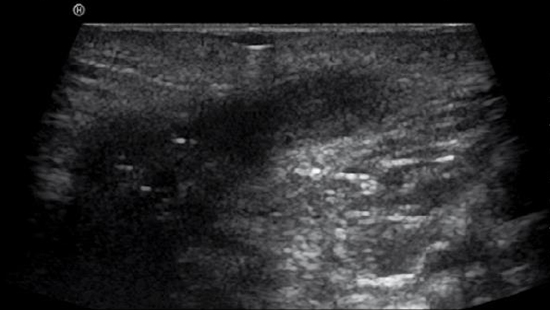

La maladie de Crohn, en particulier, implique une hypervascularisation de la paroi intestinale inflammatoire qui est facile à identifier sur une image en mode B couleur. Le score de Limberg a été développé afin de permettre une évaluation semi-quantitative. Il démontre une corrélation significative avec l’activité clinique (mesurée par le score CDAI)12. L’augmentation de la perfusion de la paroi intestinale et du mésentère adjacent peut aussi être évaluée à l’aide de cette méthode (voir les images de vascularisation).

Toutefois, il convient de tenir compte du fait que les signaux de perfusion peuvent être perturbés par le péristaltisme et les mouvements du patient, voire apparaître comme des artéfacts dus au mouvement.

D’un point de vue technique, pour détecter les petits vaisseaux intrapariétaux, l’intensité du Doppler doit être augmentée jusqu’à ce que des artéfacts de « blooming » se produisent, puis elle doit être légèrement réduite.